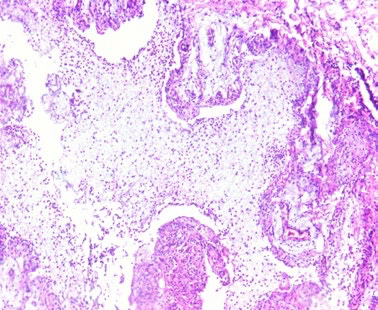

Streptococcus suis: claves diagnósticas desde la lesión hasta el laboratorio